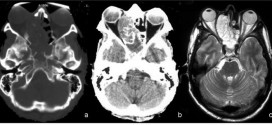

SÍNDROME BULBAR LATERAL

El síndrome bulbar lateral. Síndrome provocado por alteraciones vasculares que afectan la zona lateral del bulbo raquídeo; se caracteriza por hemiplejía alterna y hemisíndrome cerebeloso en el lado de la lesión. Puede ir acompañado de parálisis del velo del paladar, de la laringe, de la faringe y de trastornos motores y sensitivos de los miembros del lado opuesto. Para todas …